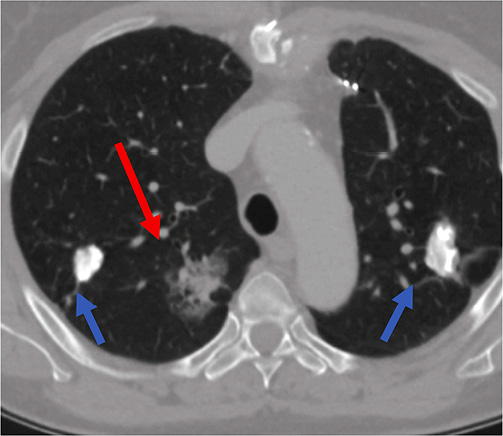

62-year-old female with smoking history of 35 pack years was referred to interventional radiology department for a biopsy of the right lung lesion. The lesion was found accidentally during CT investigation before planed aortocoronary bypass surgery. At 6-month follow-up the subsolid lesion remained stable while its suspicious appearance as subsolid nodule with ground glass area at its periphery indicated to perform a biopsy (Figure 1).

Lung biopsy procedure was performed under local anesthesia in a prone position and the patient was instructed of shallow breathing. 17 gauge coaxial needle was inserted under CT guidance and proceeded up to the lung needle while lung biopsy was performed with 18 gauge needle with automated biopsy gun (Figure 2) sampling two biopsy specimen cores.